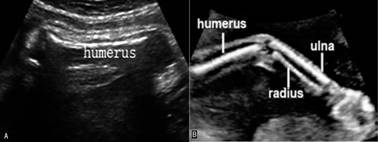

显示胎儿颈部下方横切面、胸廓上部脊柱两侧前方各有一近似“S”形的强回声向外方展开,此为锁骨回声;在胸廓后方显示为三角形的强回声为肩胛骨(图2 SC);肩胛骨上方外侧在肩峰处与锁骨接近;以此为中心旋转探头即可显示出肱骨(humerus)回声(图3A);沿肱骨追踪扫查即能显示尺骨(ulna)和桡骨(radius)(图3B)。尺骨较长,上粗下细,与小指相连;而桡骨则相反,上细下粗,与大拇指相连。尺桡骨可显示出交叉现象。沿尺桡骨向下扫查,即可见胎儿手部,正常时胎手姿势自然呈握拳状,活动时,五指伸开时可显示手指数目及姿势。

图3 胎儿上肢骨声像图